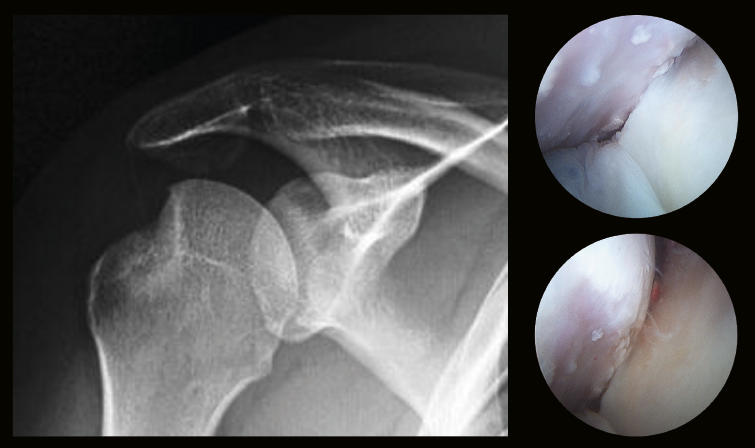

Figura 5. Lesión de Hill-Sachs on-track/no enganchante.

- LHS on-track o no enganchable: tamaño de la longitud de la LHS es menor que la longitud de la GT (LHS < GT).

- LHS off-track o enganchable: LHS > GT.

Las mediciones on-track y off-track son valores comparables a los conceptos de “lesión no enganchante o enganchante” de Burkart et al.(19), la diferencia es que las primeras se miden con una 3D-TAC antes de la cirugía, permitiendo establecer la indicación de la técnica quirúrgica más apropiada antes de la cirugía (reparación de partes blandas vs. tope óseo), y la valoración de las lesiones “no enganchantes o enganchantes” se realiza artroscópicamente (Figuras 5 y 6).